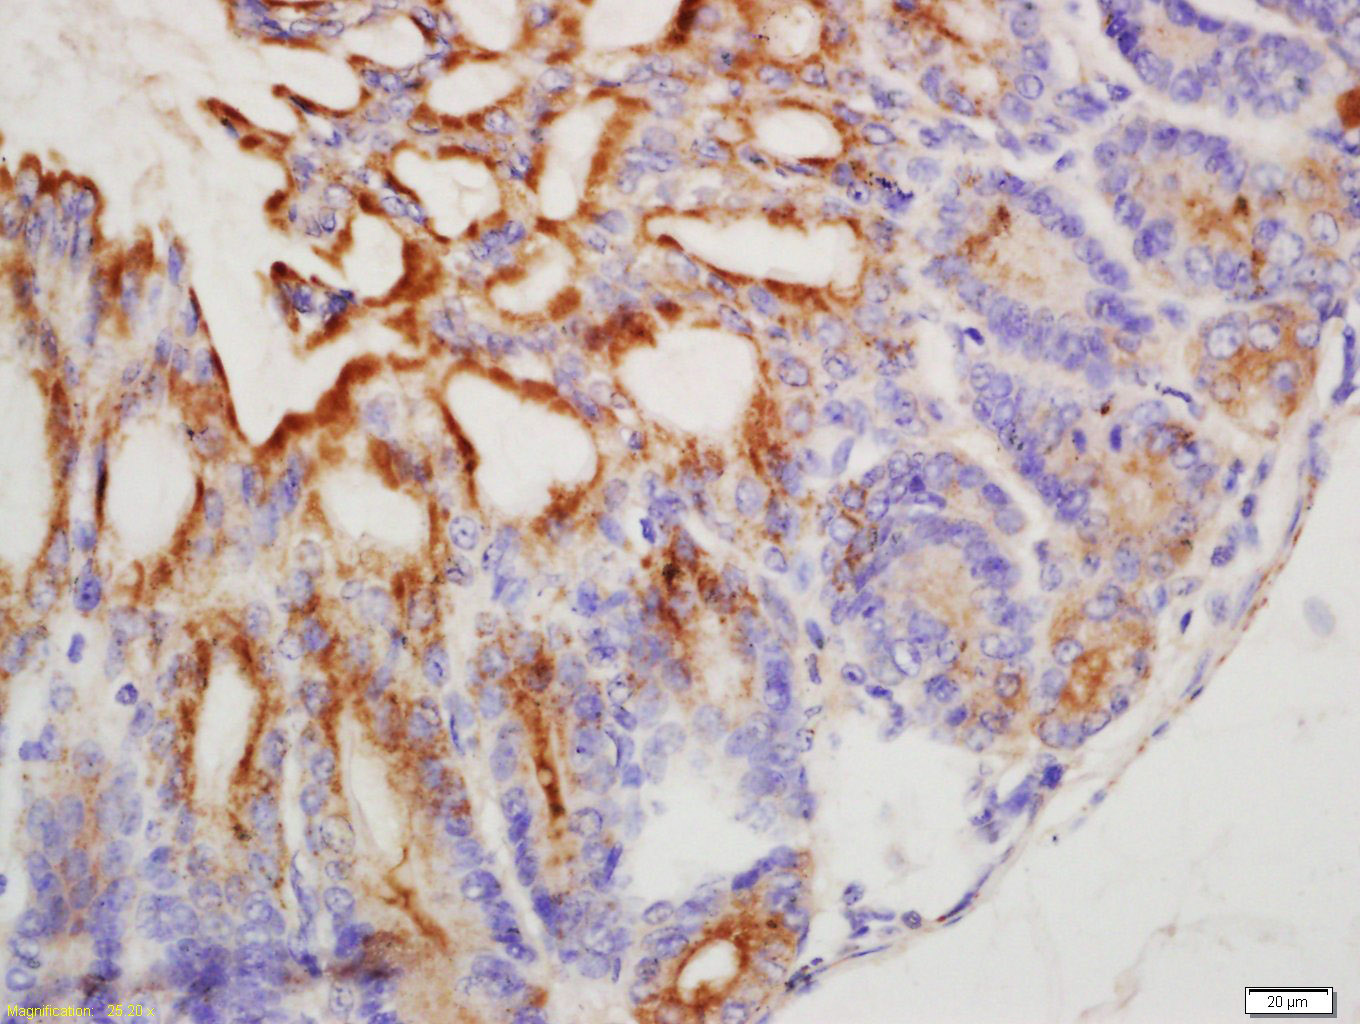

| 英文名称 | TFF1 Rabbit pAb |

| 中文名称 | 乳腺癌雌激素诱导蛋白抗体 |

| 产品应用 | IHC-P=1:100-500, IHC-F=1:100-500, IF=1:100-500 Not yet tested in other applications. |

Antigen retrieval: citrate buffer ( 0.01M, pH 6.0 ), Boiling bathing for 15min; Block endogenous peroxidase by 3% Hydrogen peroxide for 30min; Blocking buffer (normal goat serum,C-0005) at 37℃ for 20 min;

Incubation: Anti-TFF1 Polyclonal Antibody, Unconjugated(bs-6593R) 1:200, overnight at 4°C, followed by conjugation to the secondary antibody(SP-0023) and DAB(C-0010) staining